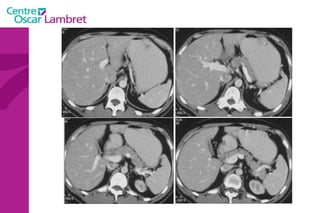

Tube Digestif Oesophage

Œsophage : transit opaque cardia 1/3 sup = de C6 à T4:  25 cm des arcades dentaires 1/3 moyen = 25 à 28 cm     Région sous-carinaire  1/3 inférieur = 28 à 35 cm